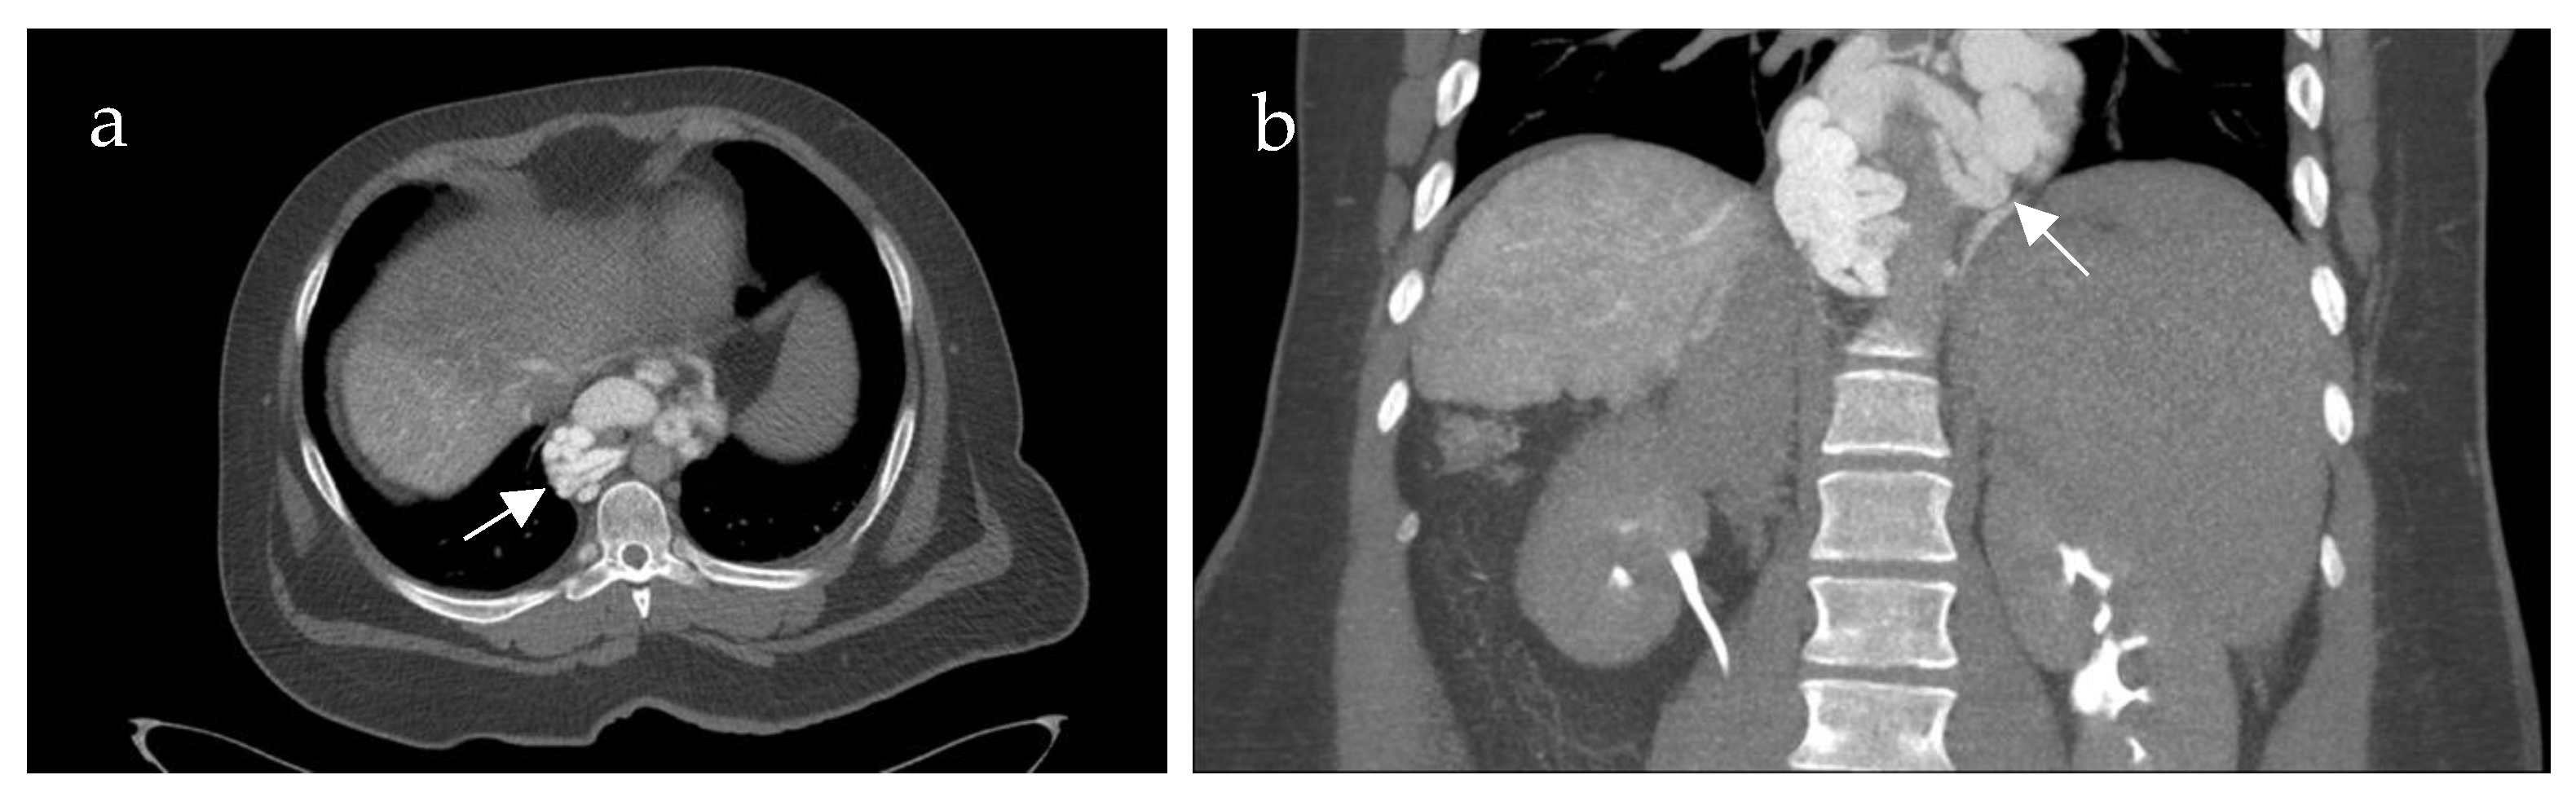

Inflow into esophageal, gastric and small bowel varices differed significantly between patients with PVCT (p = 0.021, p = 0.016 and p = 0.031, respectively) compared to patients without PVCT. In patients with PVCT, esophageal varices were fed solely by the SV in 75% (n = 9, example shown in Figure 3), solely by the mesenteric vein system in 8% (n = 1) and by both systems in 17% (n = 2, example of this rare case shown in Figure 4). Patients without PVCT showed a more equal distribution of inflow hemodynamics: esophageal varices were fed by solely the SV system in 22% (n = 2), by solely the SMV system in 22% (n = 2) and by both systems in 56% (n = 5, example of this is shown in Figure 5). In patients without PVCT, gastric varices were fed by the SV (22%, n = 2), by the SMV (11%, n = 1) or both (22%, n = 2). In contrast, 59% of the patients with PVCT (n = 7) showed gastric varices which were fed only by the SV. In 33% of cases (n = 4), both the SV and SMV drained into gastric varices. No inflow into gastric varices solely from the SMV was detected. These results were statistically significant (p = 0.016).

Figure 5. Patient of 61 years of age with portal hypertension and isolated portal vein thrombosis without involvement of the confluence. The computed tomography spleno-portography (a) shows contrasted esophageal varices (EV). The computed tomography mesenterico-portography (b) also shows contrasted EV. The EV are therefore fed by both the superior mesenteric vein and the splenic vein (white arrows). Contrast-enhanced computed tomography (c) after intravenous injection of contrast medium shows low contrast of all tissues and vessels. It does not reveal clearly distinguishable varices in the esophagus.